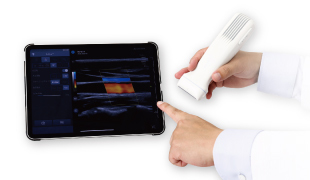

装置本体をプローブに詰め込み、プローブに内蔵されたWi-Fiを使用してモバイル端末(PC、タブレット、スマートフォン)と無線接続。院内での使用はもちろん、プローブとモバイル端末を持ち出せば、検査場所は無限に広がる。もちろん操作性も抜群。使用者の使いやすさを極限まで追求することで、熟練者はもちろん、初めてのエコーも強力にサポート。

プローブとモバイル端末のみで使用できるため携帯性に優れ、院外へ持ち出しての検査を強力にサポート。SONON500Lは従来製品(300L)と比べ、体積47%減、重さ25%減と、さらなる小型・軽量化を実現。さらに、次世代超音波エンジンを搭載。有効チャンネル数も大幅増により、ソフト・ハード両面から画質向上を実現しました。

Wi-Fi無線接続のためどこでも使用可能

プローブに内蔵したWi-Fiを使用して、モバイル端末(PC、タブレット、スマートフォン)とワイヤレス接続。ネットワーク環境に依存しないため、院内はもちろん、フィールドや訪問診療など、ネットワーク環境がない場所でも使用可能です。また、コードによる煩わしさから解放され、初めてのエコーでも当てること・見ることに集中できます。